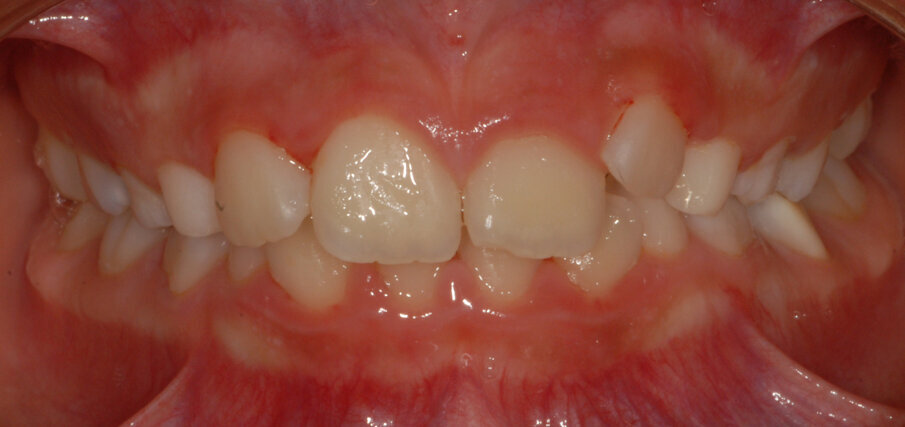

La piccola Sofia viene sottoposta a una prima visita ortodontica all’età di 8 anni, l’esame obiettivo (Figg. 1, 2) e l’ortopantomografia (Fig. 3) delle arcate dentarie evidenziano una mancanza di spazio per la corretta eruzione dei canini superiori (1.3-2.3).

Fig. 1_Foto frontale iniziale.